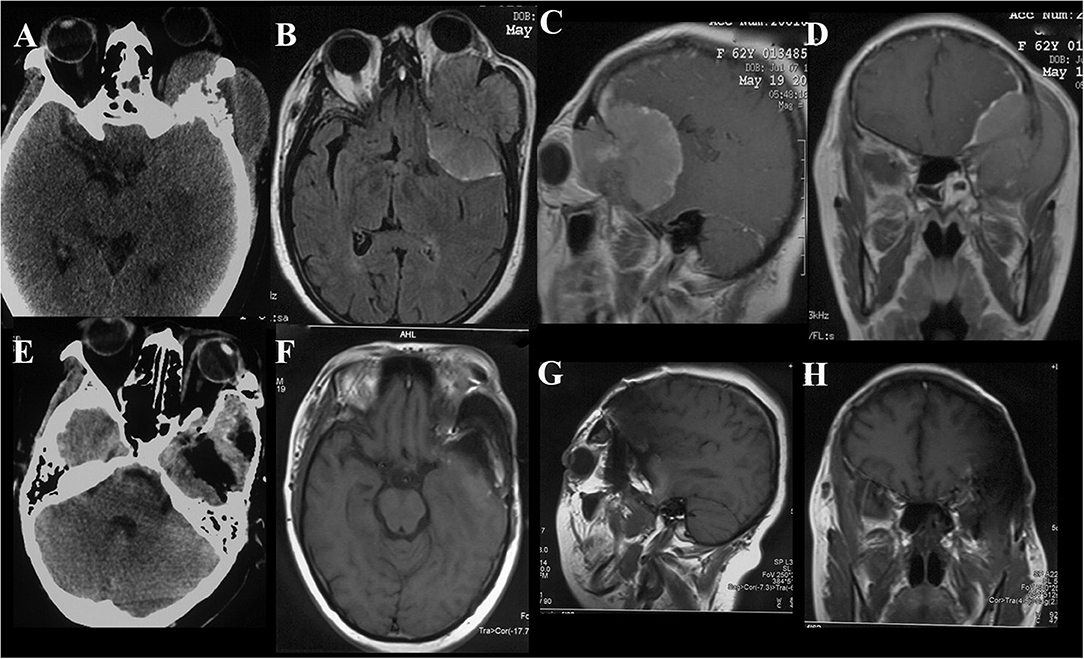

FIGURE 1

Figure 1. Case illustrating the Derome approach. (A,B) CT scans show an anterior skull base tumor with nasal extension with significant calcifications. (C,D) T1-weighted sagittal and axial contrast-enhanced MRIs show the same tumor as A and B, the irregularly shaped lesion with heterogeneous enhancement and cystic changes. (E) A periosteal flap was prepared for repairing the skull base defect. (F–H) Postoperative contrast-enhanced MRIs indicated GTR of the tumor.